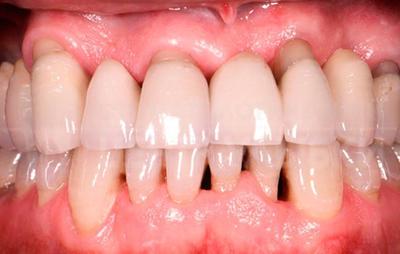

- Выпадение зубов из-за их системного расшатывания

При тяжёлой форме заболевания, когда глубина пародонтального канала превышает 6 мм, а дёсны гноятся и кровоточат, происходит поражение периодонтальной связки. Чем оно глубже и обширнее, тем сильнее расшатывается зуб. Чаще зуб подлежит удалению, но в ряде случаев возможна фиксация зуба при помощи шинирования.